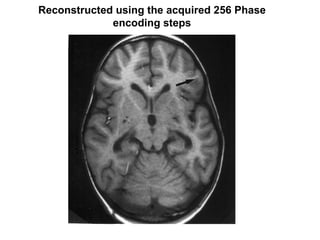

- 1. Reconstructed using the acquired 256 Phase encoding steps